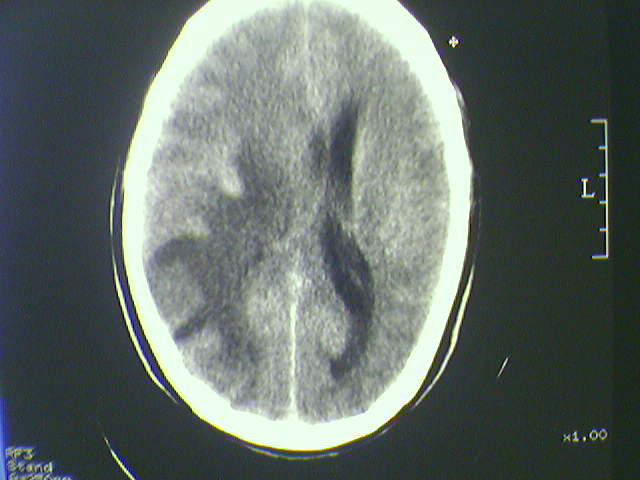

标题: CT21792:男48岁,头痛昏一月加重伴双下肢无力一天,反应迟 [打印本页]

标题: CT21792:男48岁,头痛昏一月加重伴双下肢无力一天,反应迟

病史不详;支持脑转移瘤诊断。

支持脑转移瘤诊断。

多发转移瘤

水肿占位效应明显,支持脑转移瘤诊断

支持 多发性脑转移瘤。